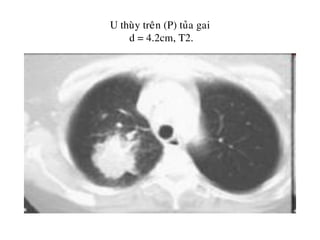

U thuøy treân (P) tuûa gai

d = 4.2cm, T2.

Haïch tröôùc khí quaûn, T2N2